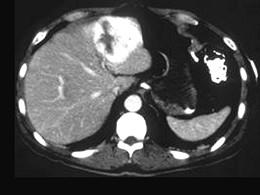

问题 男,40岁,中上腹胀疼不适,CT扫描如图,最佳的诊断为 ( )

选项 A、肝血管瘤 B、肝血管内皮瘤 C、胆管细胞癌 D、肝转移瘤 E、原发性肝癌

答案 A